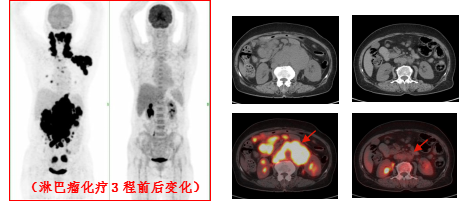

治疗前 治疗后

淋巴瘤治疗前后变化: 弥漫性大B细胞淋巴瘤化疗3程后,腹腔及腹膜后多发肿大淋巴结明显缩小,糖代谢明显减低。

(上两图为:治疗前,下两图为:治疗后)

淋巴瘤治疗前后变化:弥漫性大B细胞淋巴瘤化疗3程后,腹腔机腹膜后多发肿大淋巴结明显缩小,糖代谢明显减低。根据Deauville标准 5PS评分为2分。